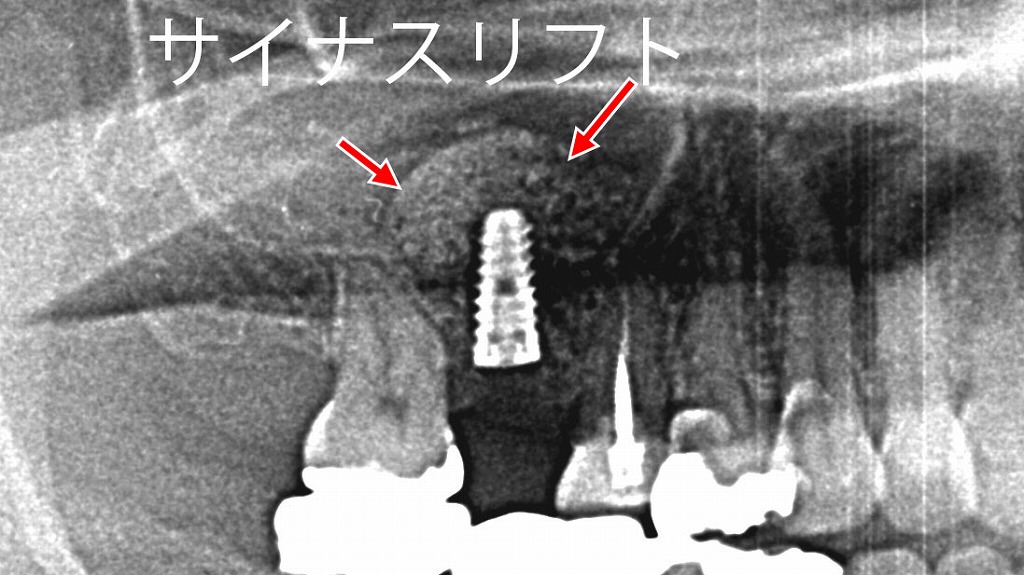

サイナスリフトを伴うインプラント手術

上顎奥歯は骨の高さが不足しやすく、そのままではインプラントを埋入できない場合があります。

この症例では、上顎洞(サイナス)を持ち上げて骨補填材を填入するサイナスリフトを行ったうえで、インプラントを埋入しています。

サイナスリフトを伴うインプラント手術の所要時間は、

片側1本あたりおおよそ60〜120分程度が目安です。

骨の状態や同時埋入の可否、処置範囲によって前後しますが、事前の精密検査と計画により安全に進めることが可能です。